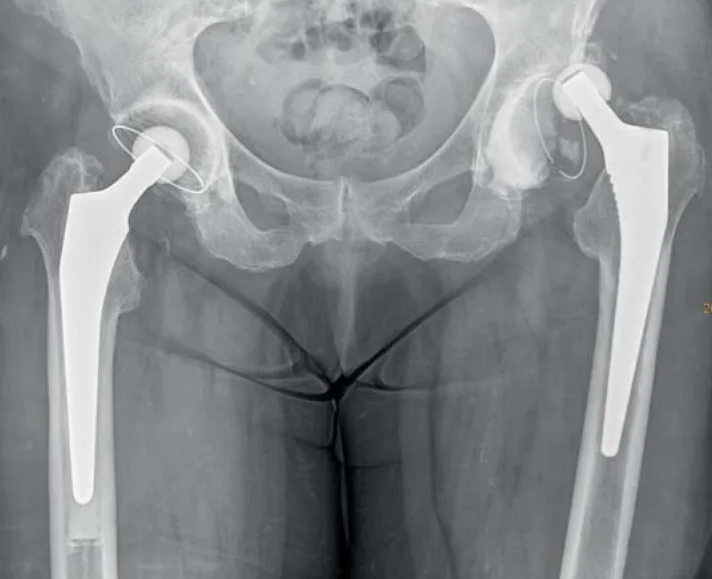

В случае перелома шейки бедра компания МосРентген Центр госпитализирует в Склиф для эндопротезирования.